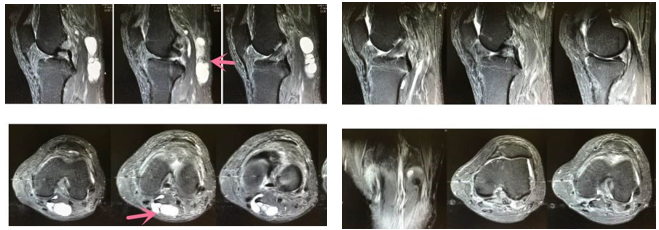

左图为关节镜术前(红色箭头所示为囊液)

右图为关节镜术后6个月,囊肿消失